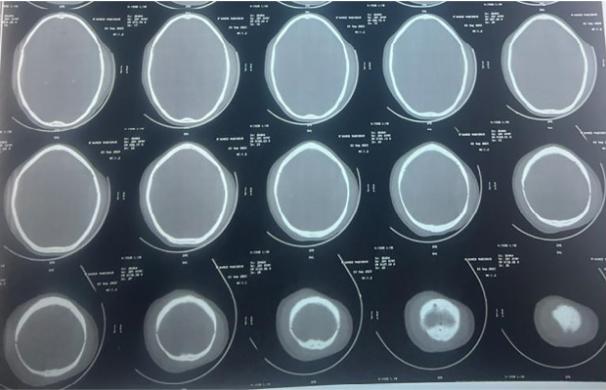

计算机断层扫描(CT)显示双侧对称的顶叶EDH,右侧为25mm,左侧为23.5 mm,少数右侧顶骨下沟回有蛛网膜下腔出血[图1]。骨窗显示双顶骨骨折线[图2]。

图1、扫描显示双侧顶叶ED